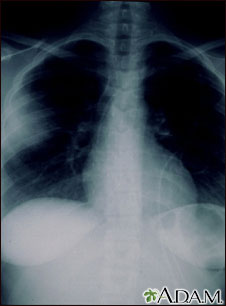

Your health care provider may suspect you have a fungal infection after x-rays of your lungs show the ball of fungus. Other tests that may be done include: